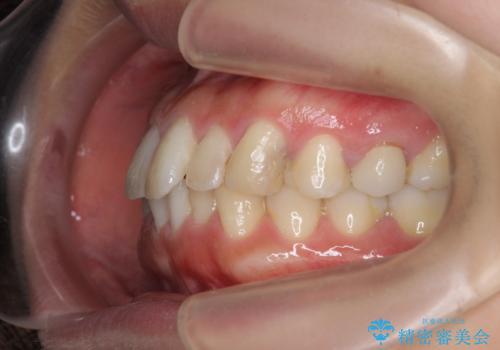

挺出小矯正を行った縁下カリエス治療

- 治療途中で虫歯治療を放置し、違和感が強くなってきたためしっかりとした虫歯治療を行いたいと希望され来院されました。

X線撮影を行い、隣接面に多発した虫歯と歯ぐきよりも深くなってしまった虫歯を小矯正をおこなったのちのセラミック治療で問題を解決します。